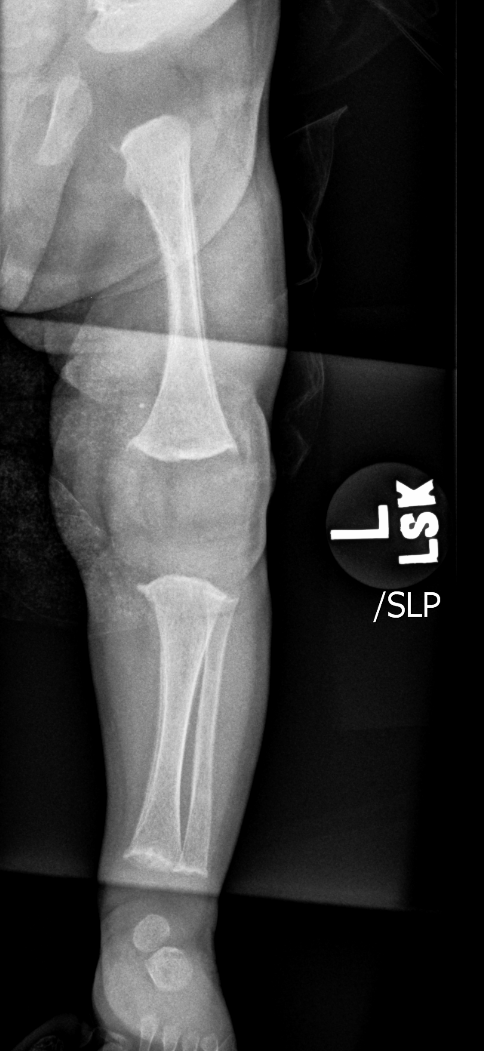

Findings

Bone

Growth plates, ossification centers, apophyses

Joints and alignment